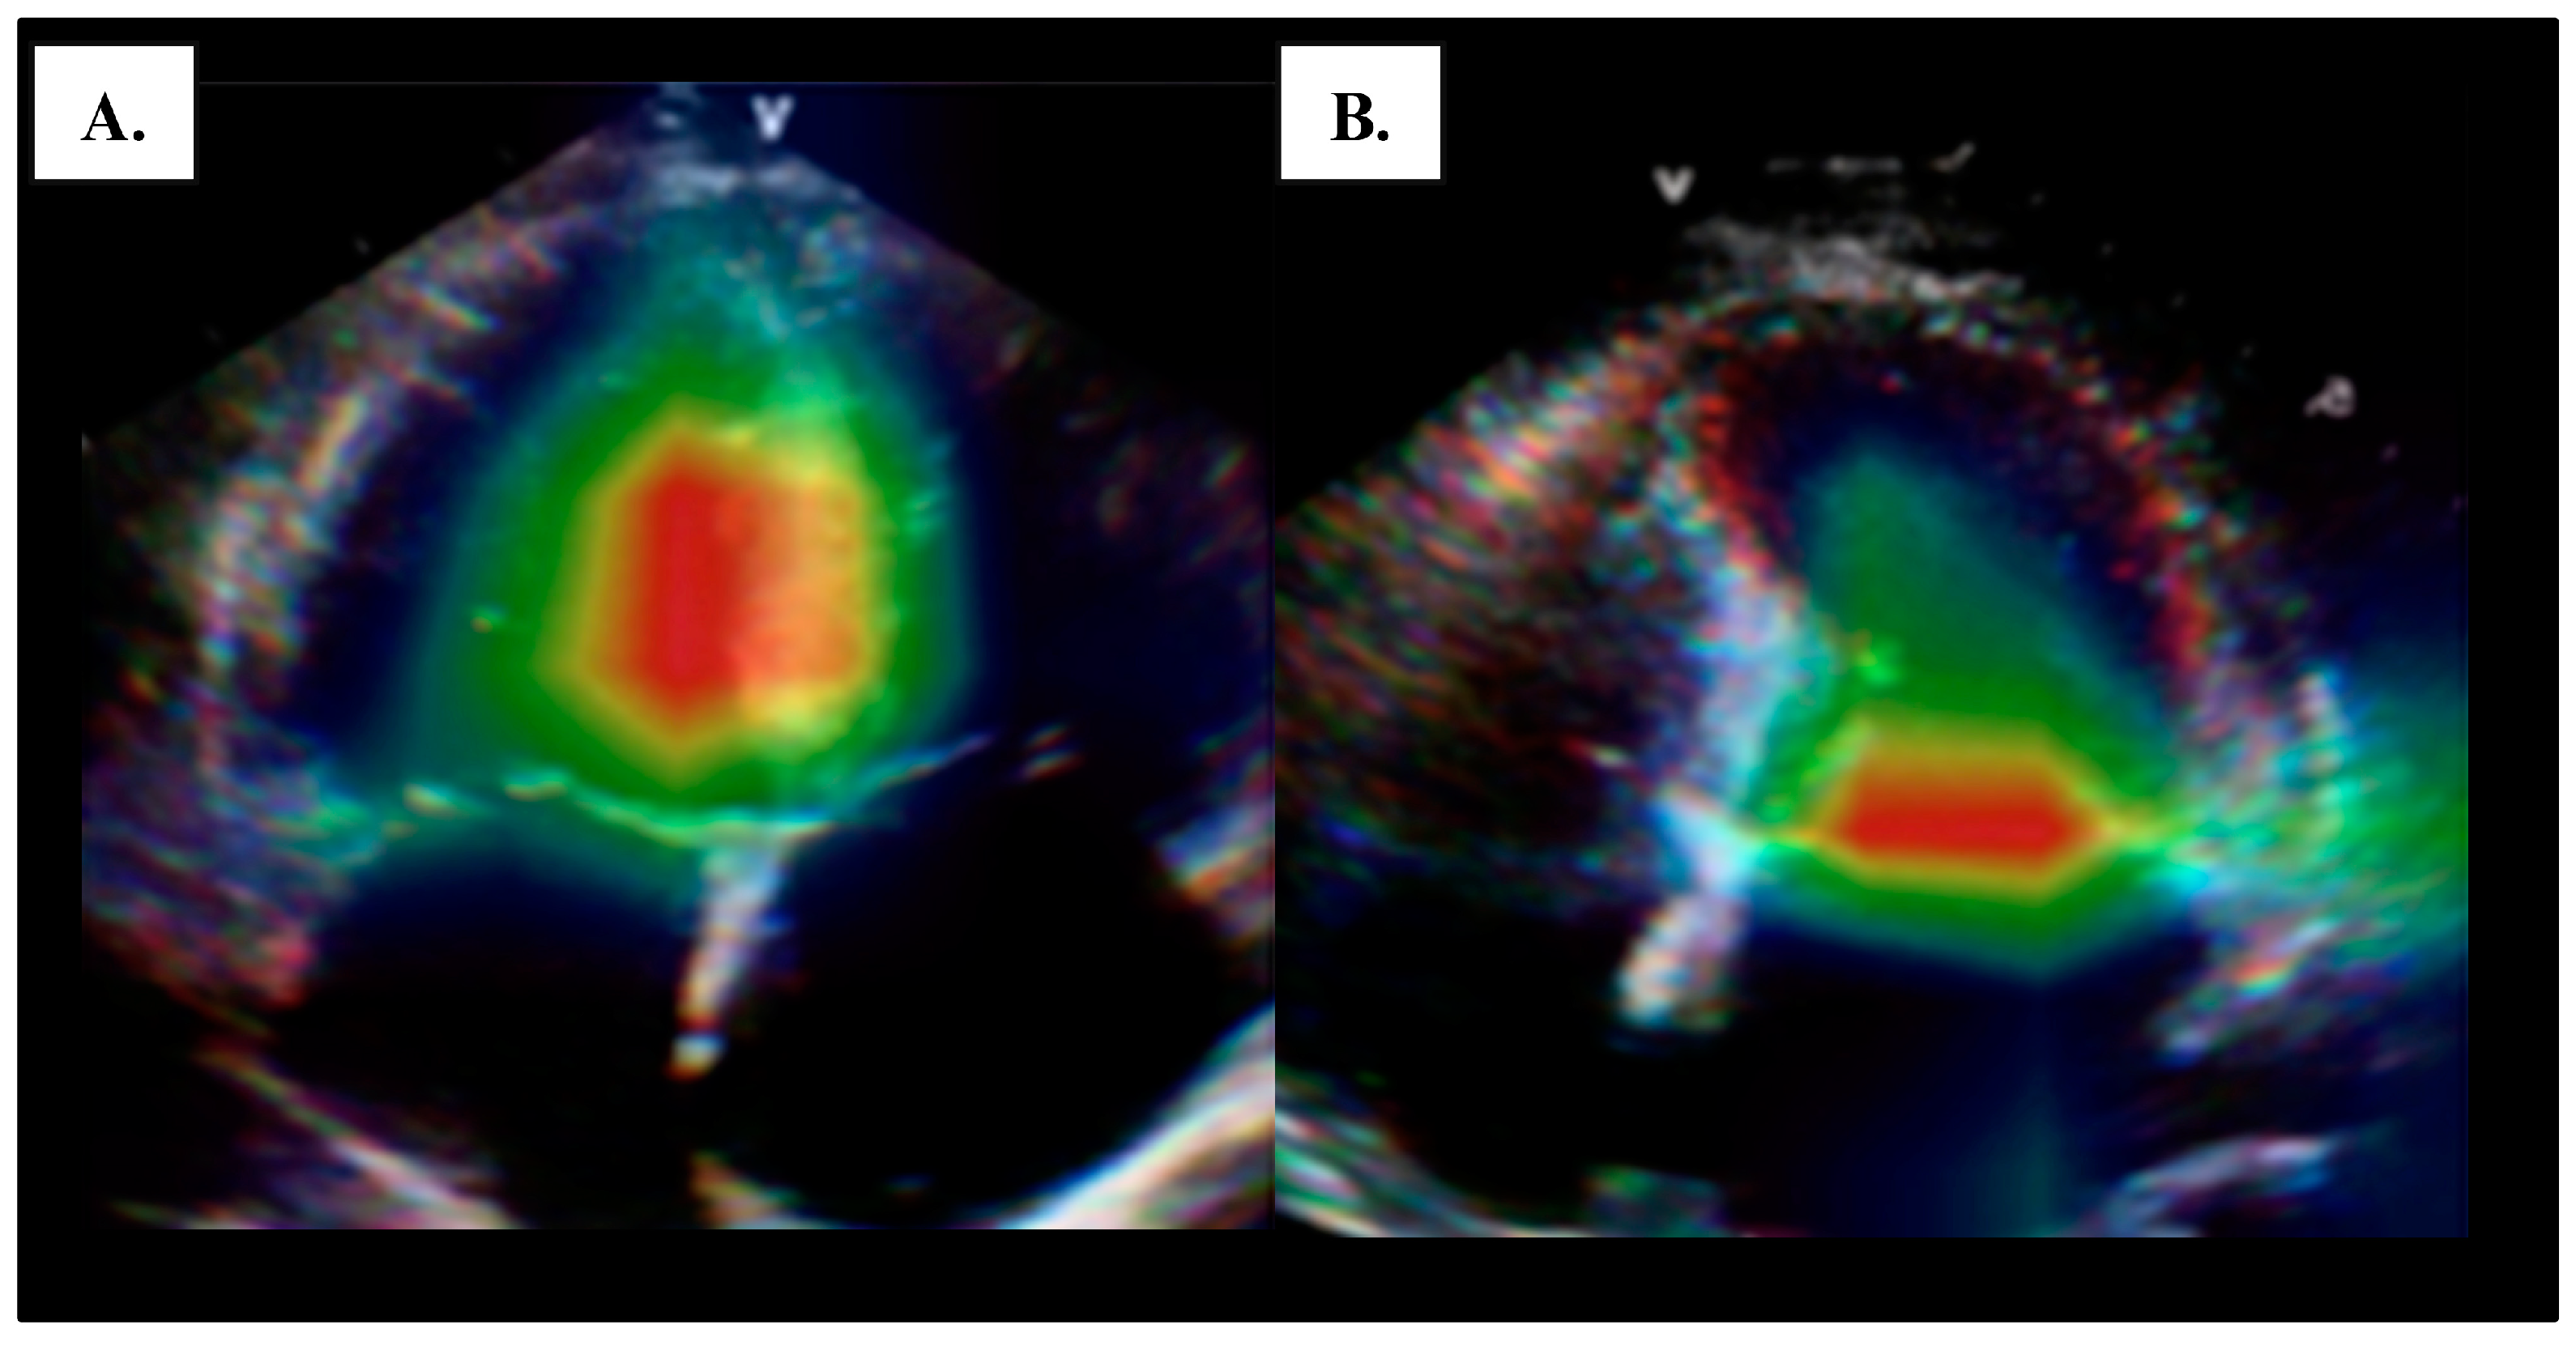

4.1. Left Ventricular Systolic Function

4.2. Global Longitudinal Strain